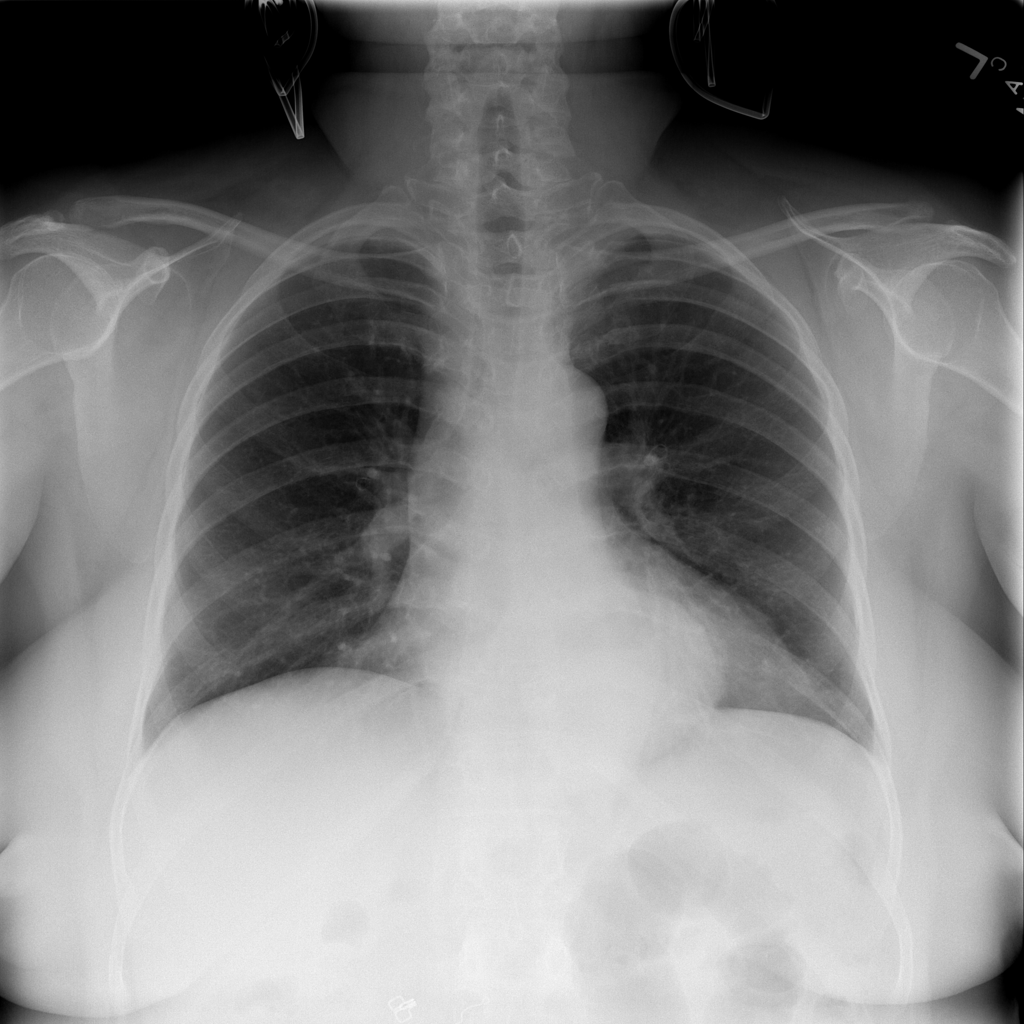

PAT-C048 · IMG-000Hernia

PAT-C048 · IMG-000

PA